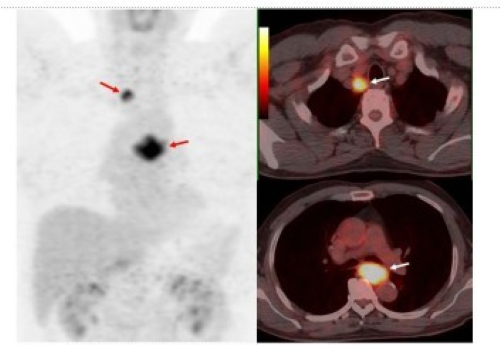

4. PET/CT Scan.